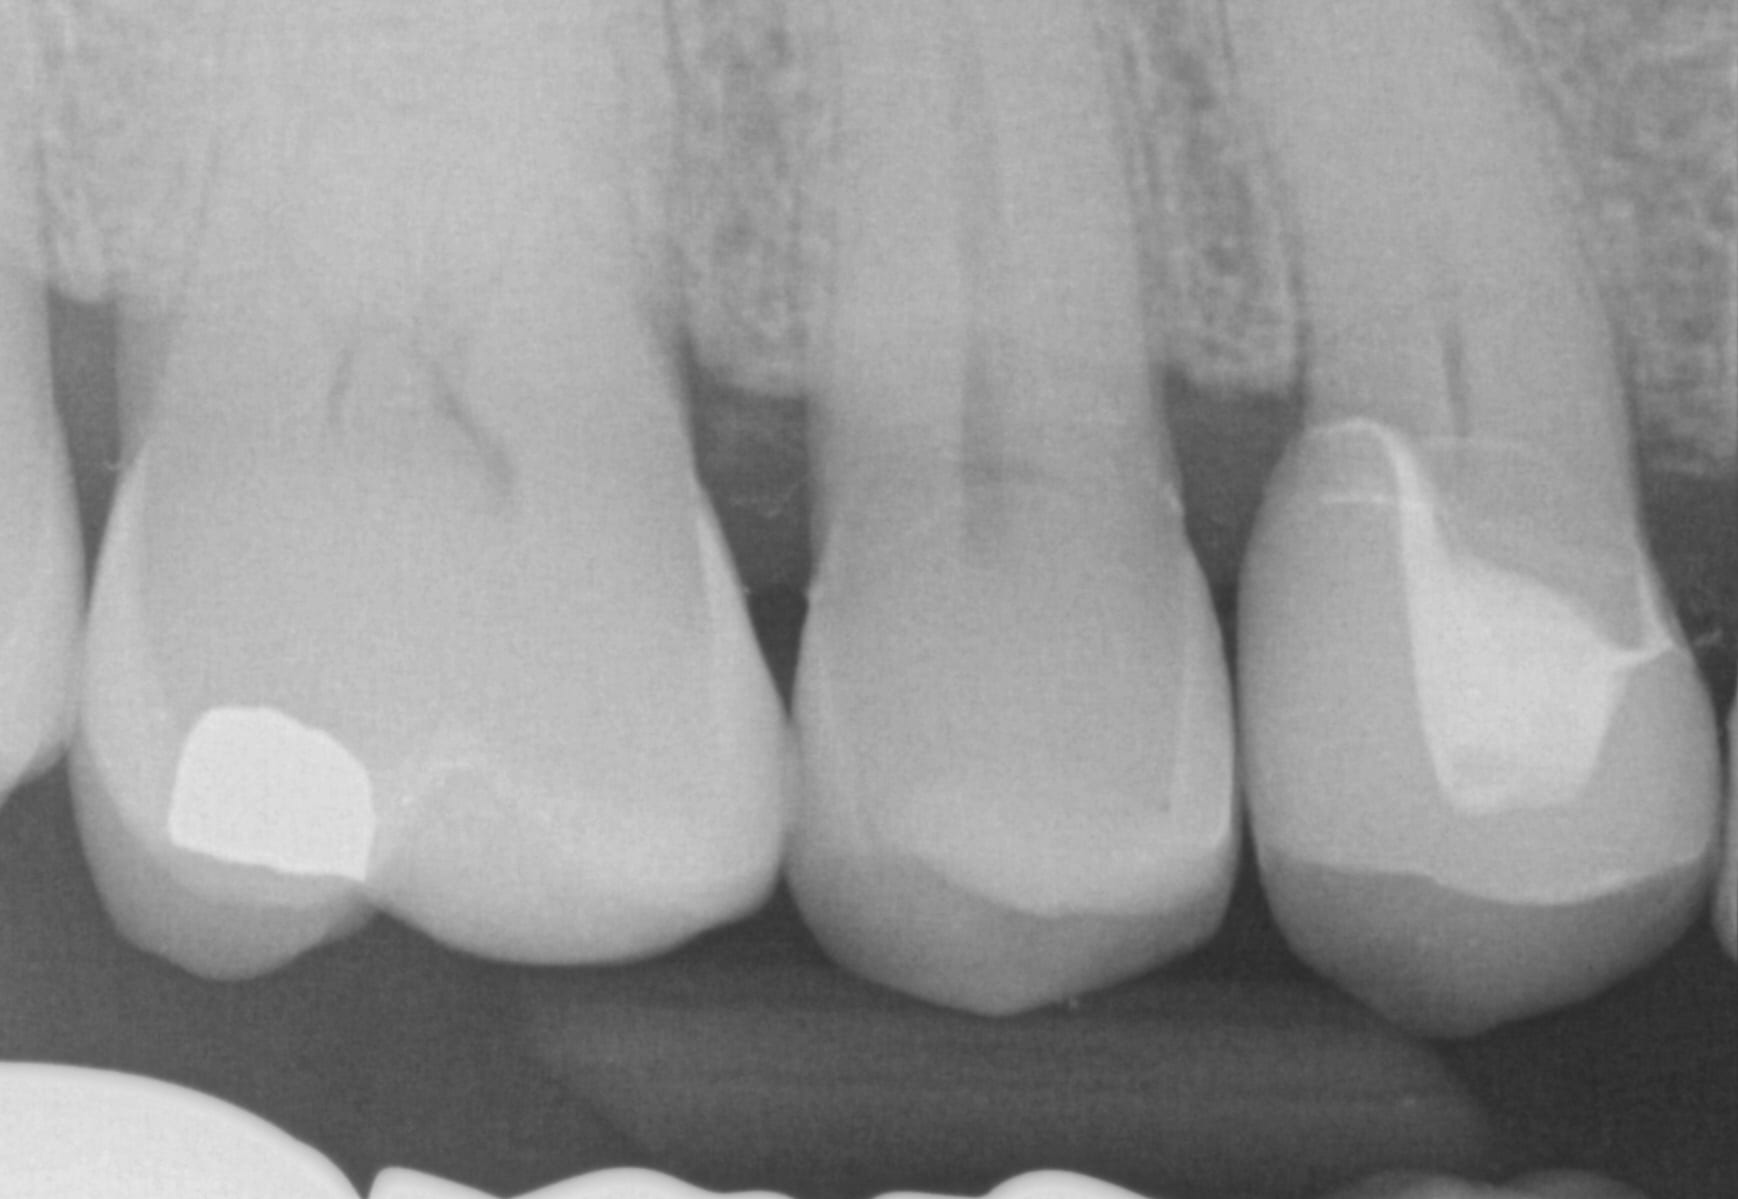

In this case presentation, we utilize the medit i500 to image the pre-existing crown and to fabricate a restoration that is a replica of the pre-existing condition. The patient was advised that the recurrent decay was in close proximity to the canal space and that endodontic treatment may be a possibility. The CBCT showed no evidence of any peri-apical radiolucency and the premolar tested vital prior to treatment

Case set up involved imaging the pre-existing condition in the pre-op catalog box. Excess information was cropped to reduce file size. The data was then copied to the maxillary arch catalog box and the area to prepared was edited out in preparation for final optical impressions.